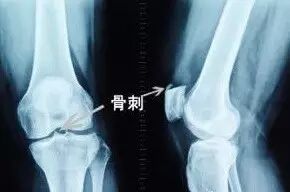

骨刺临床上称为骨质增生,多发于中年以上。这是因为随着年龄的增长,骨关节也会逐渐退化,当骨头与软组织接触的地方因长期承受压力、拉力、损伤,造成关节间的软骨渐渐失去水分与弹性,骨头与骨头磨损,人体为了减小骨关节之间的压力,在骨关节边缘上自然而然就会增生一部分来减少这个压力。它本质上是人体生理上的代偿功能,是人体为适应力的变化而产生的一种自我保护反应。

体重超标会加重机体负重关节的负担,使得关节软骨过度受损、受累,引起骨质增生。同时,在体重增加的同时,膝关节的肌肉、韧带等维持关节稳定的软组织并不会增加,关节的稳定性减弱,在活动时关节易发生拉伤、扭伤等,这些都是诱发骨质增生的因素。

大多数人听到有“骨刺”就立即想到拔刺。其实大可不必如此,骨刺是骨关节退化的一种表现,就如同人老了,头发会变白,眼睛会“老花”一样。如果没有明显症状就不需要进行特殊治疗,所以大家大可不必谈“骨刺”就色变。对于“骨刺”大多可以采取保守治疗,保守治疗无效者才需要手术。